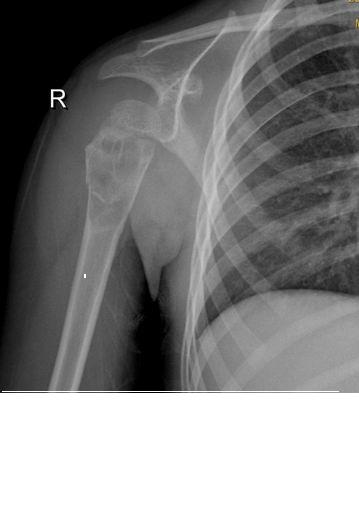

标题: X5828:骨囊肿

一小时前肩关节受外伤,一年前有外伤史

肱骨近端骨质呈多房囊状膨胀性改变,与骨干长轴方向一致,未突破骺软骨板,边缘见硬化,骨壳欠完整,可见“骨折片陷落征”,内见多个残留长短不一骨棘,软组织影无肿胀。

鉴别诊断:1、骨囊肿,典型发病年龄及部位,可见病理性骨折,较支持,不支持点是骨质膨胀较明显;

2、骨纤维异常增殖症:单骨多囊状破坏,外缘光滑,内缘毛糙波浪状,囊内外条索状骨纹及斑片状致密影具有特征性;

3、软骨母细胞瘤:骨骺部位偏心性病变,可跨越骺板;

4、abc,未突破骺软骨板,骨质膨胀;

5、软骨母合并abc。

考虑:骨囊肿合并病理性骨折可能性大,需排除骨纤、软骨母合并abc等。